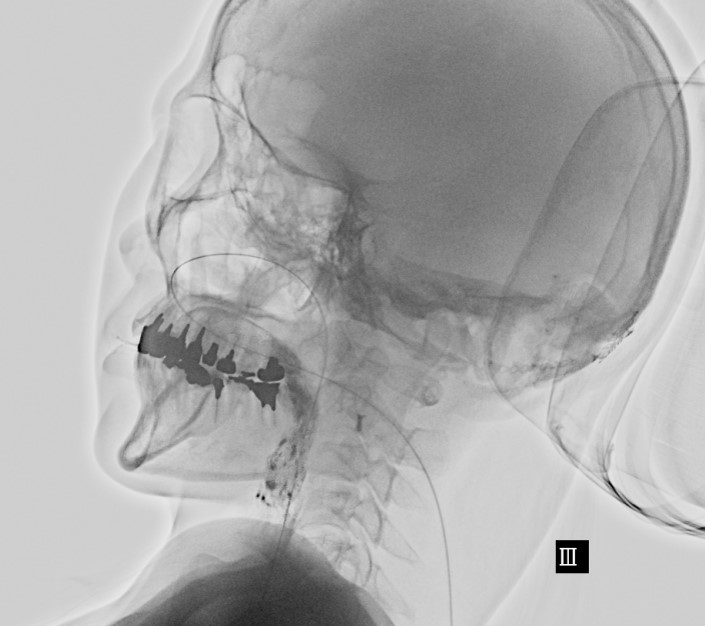

• ST-VF検査

脳疾患の装具外来、手外科スプリント療法、VF

【ST】コミュニケーション障害、嚥下障害に対する電気刺激療法、高次脳機能障害、VFなど